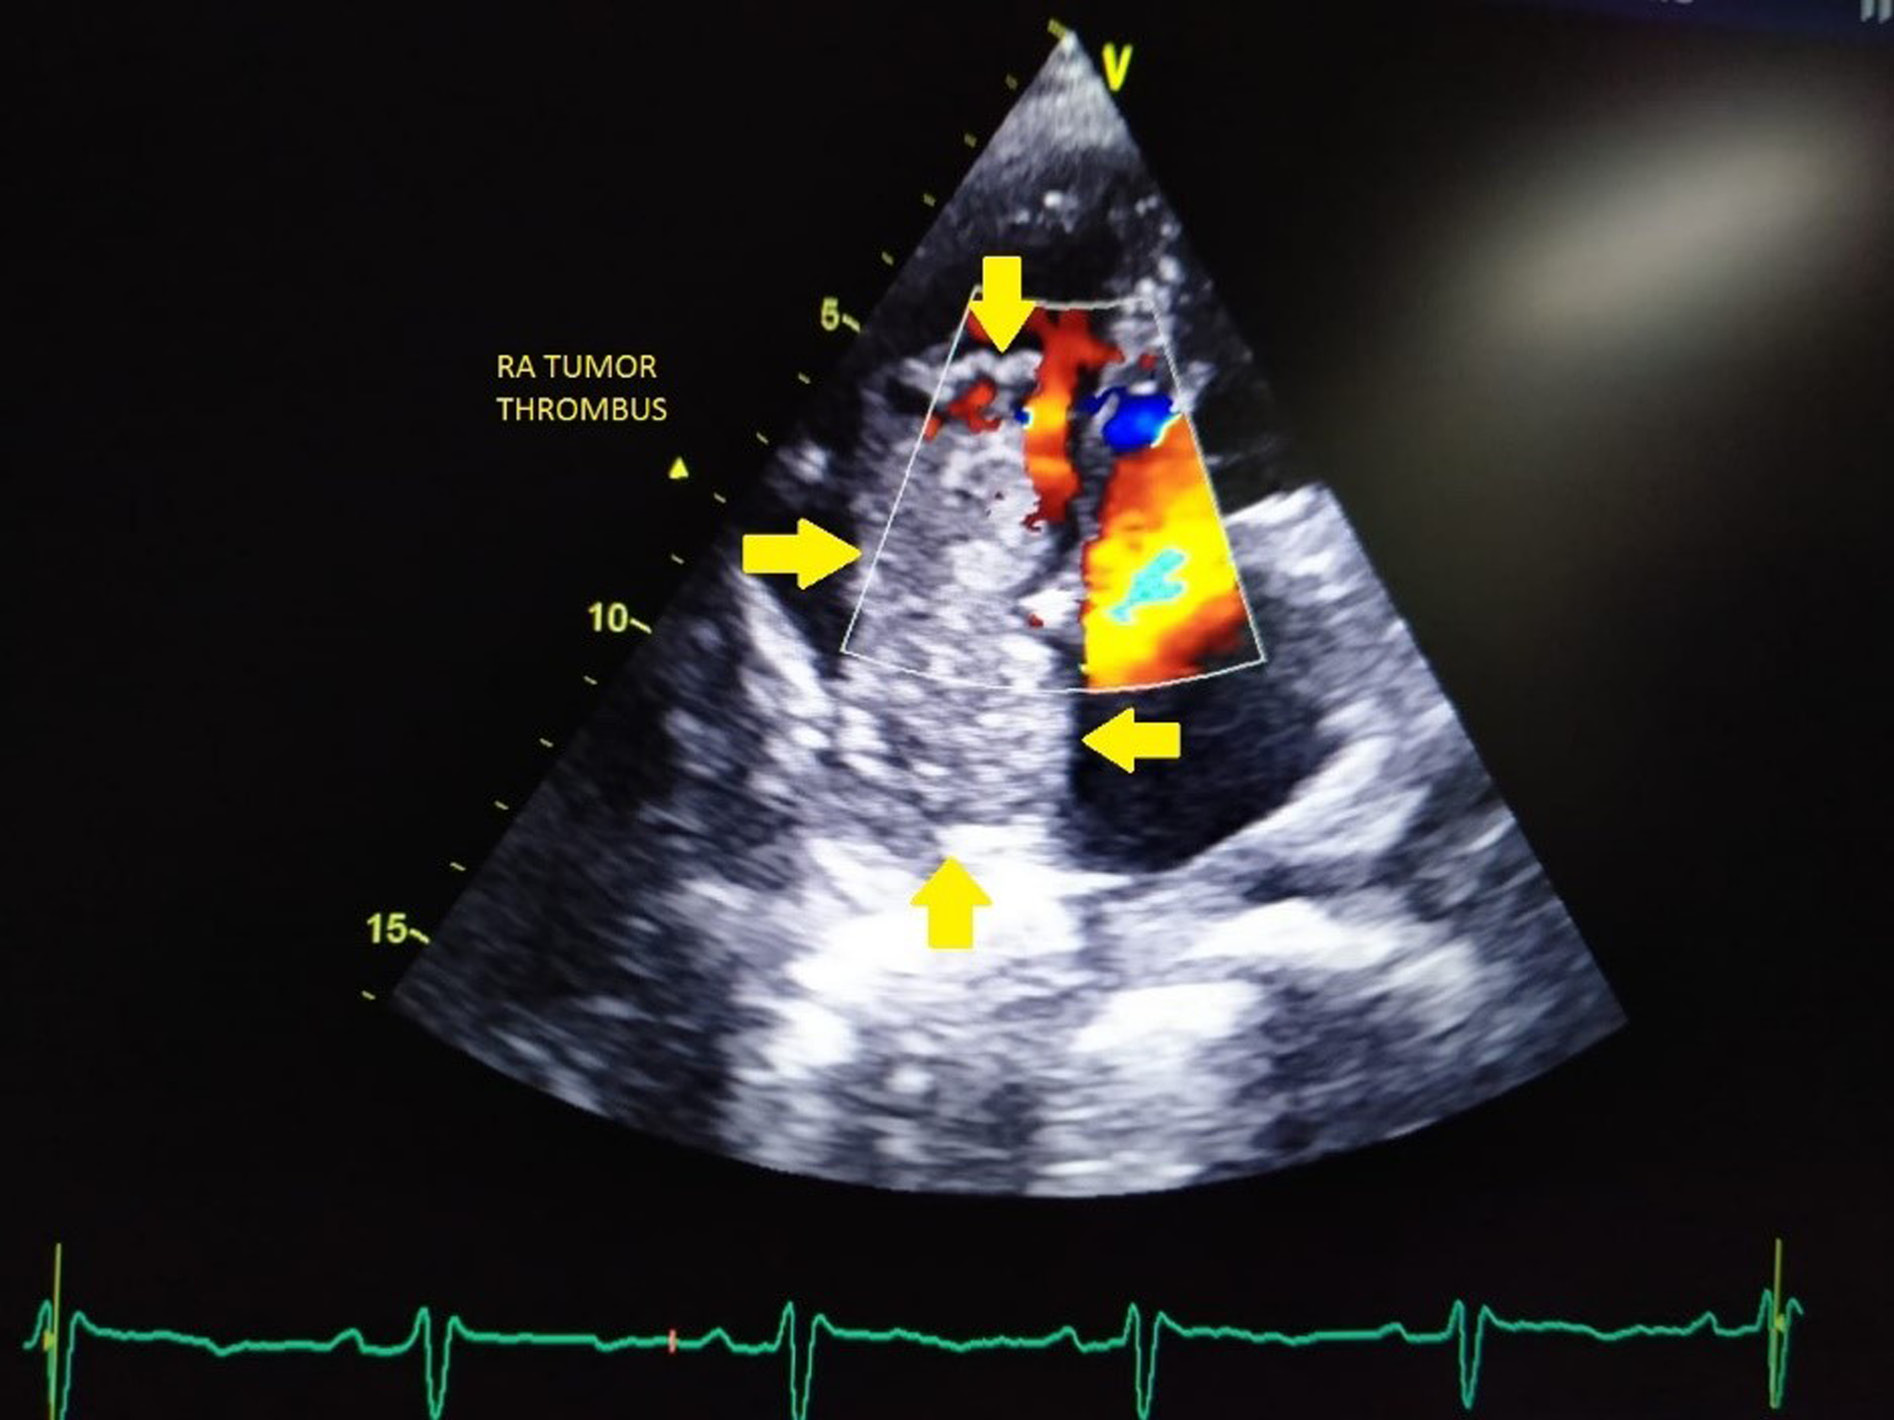

His blood tests for hepatitis B virus (HBV) surface antigen, hepatitis B virus (HBV) core IgM antibodies, hepatitis C virus (HCV) antibodies, and human immunodeficiency virus (HIV) type 1 (HIV-1) p24 antigen and HIV-1 and HIV-2 antibodies were negative. Other laboratory results (normal ranges in parentheses) were as follows: Haemoglobin, 9.4 gm/dl (12–15 gm/dl); total bilirubin, 12 mg/dl (0.2–1.2 mg/dl); aspartate aminotransferase, 376 IU/l (5–40 IU/l); alanine aminotransferase, 114 IU/l (5–47 IU/l); alkaline phosphatase, 444 IU/l (111–295 IU/l); and lactate dehydrogenase, 229 IU/l (100–225 IU/l). Ultrasonography of the abdomen revealed a large space-occupying lesion in the right lobe of the liver with the background of chronic parenchymal liver disease and portal vein thrombosis. Contrast Enhanced Computed Tomography (CECT) abdomen reveals an 11.9 × 10.8 × 14 cm hypervascular mass showing enhancement on arterial phase and rapid washout in the right lobe of liver with thrombus extending into IVC and portal vein (Figure 1). The serum α-fetoprotein (AFP) was elevated to > 54000 ng/ml (normal range <13.2 ng/ml). His electrocardiography showed normal sinus rhythm and chest X-ray showed mild right-sided pleural effusion and normal cardiothoracic ratio. A 2D transthoracic echocardiogram demonstrated a large intracardiac right atrial thrombus measuring 5.7 × 2.4 cm obstructing the tricuspid valve during the diastolic phase of the cardiac cycle (Figure 2).

Figure 2. Transthoracic echocardiography image showing a large intracardiac right atrial thrombus measuring 5.7 × 2.4 cm obstructing the tricuspid valve during the diastolic phase of the cardiac cycle (RA; arrow).